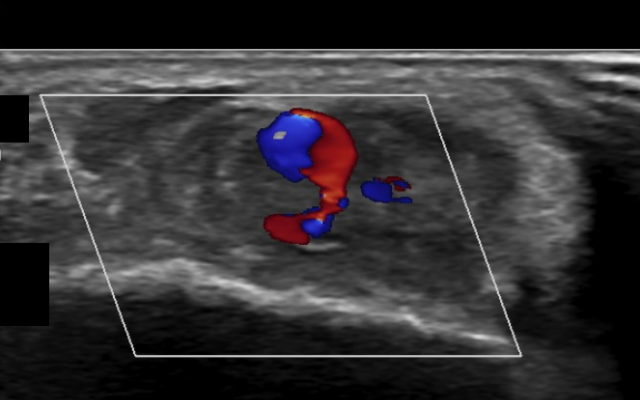

Echografisch onderzoek toonde een hematoom met daarin een hypo-echogene, pulserende vochtcollectie. Kleurendoppler-echografisch onderzoek toonde het zogenoemde yin-yangteken (figuur b) en een ‘to-and-fro’-golfbeweging, passend bij een pseudoaneurysma. Het aanvoerende vat was niet duidelijk…